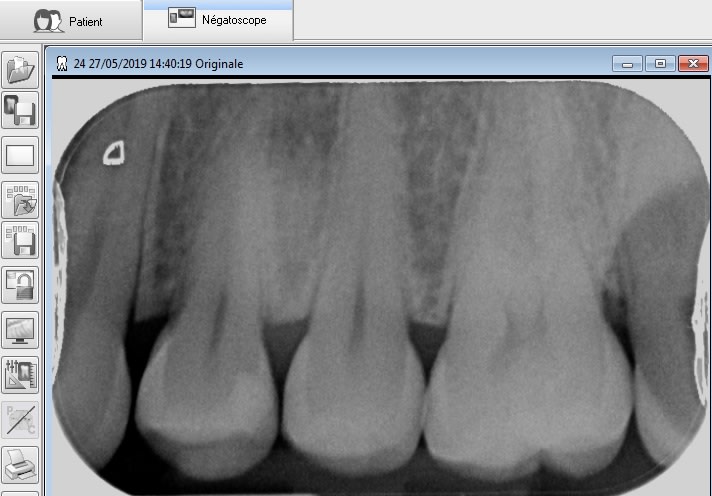

Puisque le sujet a été évoqué récemment, je relance, du matin.

J'en avais une autre prévue mais la crête a pété lors de l'éviction carieuse, pas grave mais du coup je ne pouvais pas présenter de photos.

Preuve donc que ce n'est pas si compliqué.

24 tunnel zedm1z - Eugenol

Img 4409 nlhvso - Eugenol

Img 4410 cw8ykh - Eugenol

Img 4411 cnu7fb - Eugenol